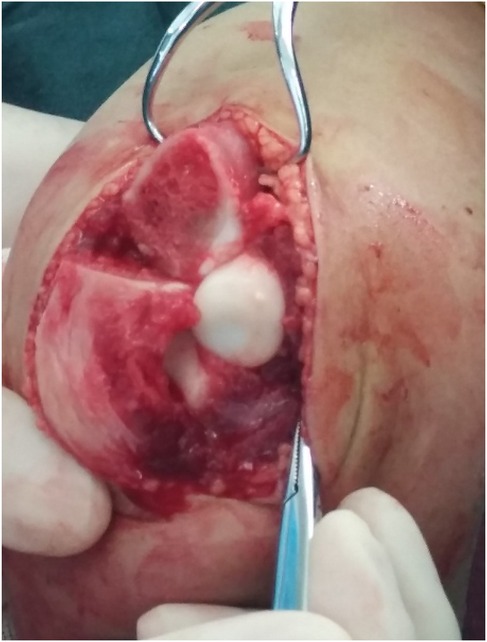

Objective: To investigate and analyze the application value of elbow arthrography in the treatment of chronic radial head dislocation in children. Methods: From January 2014 to January 2017, 15 children with chronic anterior radial head dislocation were treated (11 boys, 4 girls; average age 9 years, range 3-11 years). Intraoperative elbow arthrography was performed to assess the position of the radial head relative to the joint capsule. The nature of the dislocation was confirmed by opening the joint capsule to directly observe the relationship between the radial head and capitellum, as well as the morphology of the radial head. Reduction of the radial head was achieved via proximal ulnar osteotomy, and fixation was performed using a plate and screws with or without Kirschner wires (K-wires). Results: Elbow arthrography showed the radial head was located within the joint capsule in 12 cases and outside the capsule in 3 cases. Among the cases: All 8 congenital dislocations had the radial head within the joint capsule. Of the 7 traumatic dislocations, 4 had the radial head within the capsule and 3 outside. Direct inspection after capsulotomy confirmed the arthrography findings and revealed characteristic morphological differences. In congenital dislocations, there was no scar tissue between the radial head and capitellum, and the radial head fovea was shallow and flat. In traumatic dislocations, obvious scar tissue was present between the radial head and capitellum, and the radial head fovea was distinct. Follow-up ranged from 9 months to 4 years (average 2 years 5 months). Postoperative radiographs showed no cases of radial head re-dislocation or subluxation. Postoperative elbow range of motion improved in all patients, with no reports of pain or functional instability. Conclusion: Elbow arthrography serves as a valuable adjunct for differentiating between congenital and traumatic radial head dislocations, thereby informing both surgical strategy and the decision for supplemental fixation. When stable bony alignment is achieved, proximal ulnar osteotomy without annular ligament reconstruction represents an effective management strategy for chronic radial head dislocation in children.